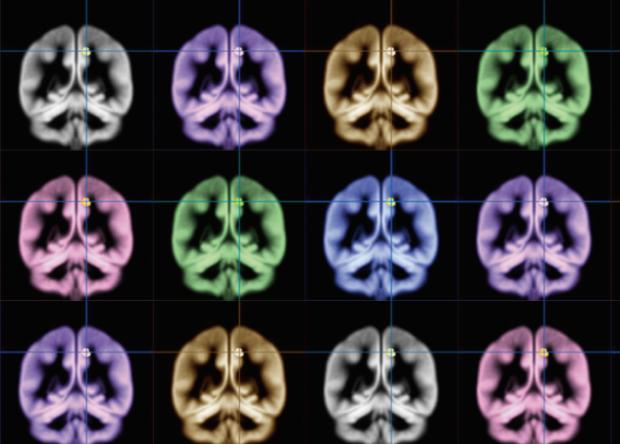

Японские учёные смогли с помощью магнитно-резонансной томографии найти область мозга, которая может отвечать за формирование чувства счастья. Исследование, опубликованное в Scientific Reports, открывает возможность к его объективному измерению.

Используя структурную МРТ, ученые получили изображения мозга всех участников исследования. Статистический анализ показал, что уровень счастья коррелирует с количеством серого вещества в одной области правого полушария – внутренней части теменной коры (прекунеусе). Ранее ученые с помощью МРТ выяснили, что возникновение у человека счастливых эмоций сопровождается активацией теменной коры головного мозга.